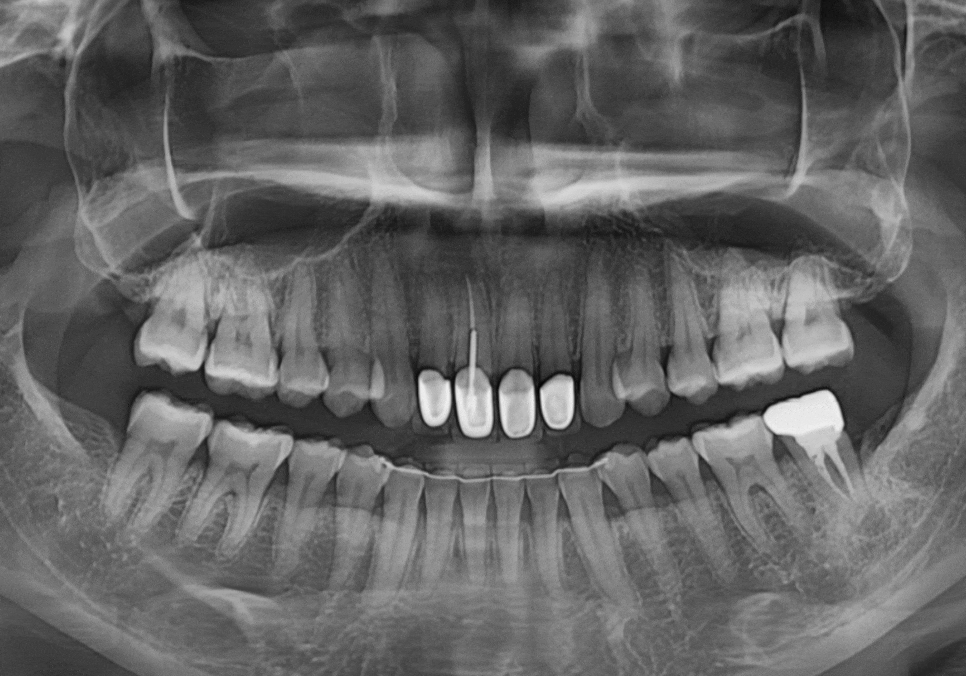

임플란트와 뼈이식, 3개월의 기다림

강동구 치아 뿌리 염증, 신경치료 한 치아인데도 아플 수 있나요?

염증 때문에 녹아버린

잇몸 뼈를 보충하기 위해

임플란트 식립과 동시에

뼈이식을 함께 진행했습니다.

다행히 수술은 아주

안정적으로 잘 마무리되었습니다.

251015

3개월 후, 잇몸 뼈와 임플란트가 하나처럼

단단히 붙은 것을 확인 뒤,

지르코니아로 맞춤 보철물까지

완벽하게 완성해 드렸습니다.^^

2050508(전) 251015(후)